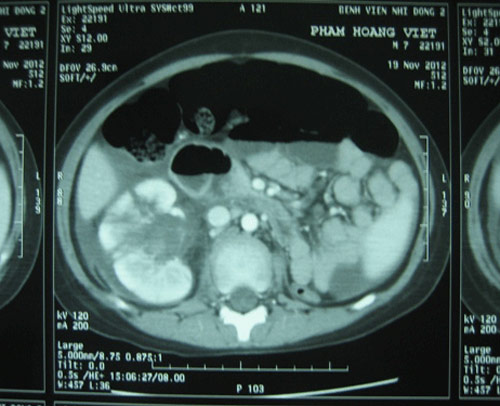

Trước đó, ngày 18-11, Việt đang đi xe đạp thì bị xe máy tông vào lưng. Sau khi té, bé thấy đau vùng hông phải, tiểu ra máu. Việt được chuyển đến Bệnh viện Nhi Đồng 2 trong tình trạng vùng hông phải bầm tụ máu, ấn đau và tiểu ra máu. Sau khi làm CT và siêu âm bụng cho Việt, các bác sĩ phát hiện bé chỉ có một quả thận. Trái thận này bị chấn thương độ V, nứt làm 3 mảnh nhưng cuống mạch máu thận vẫn còn.

Hình ảnh siêu âm